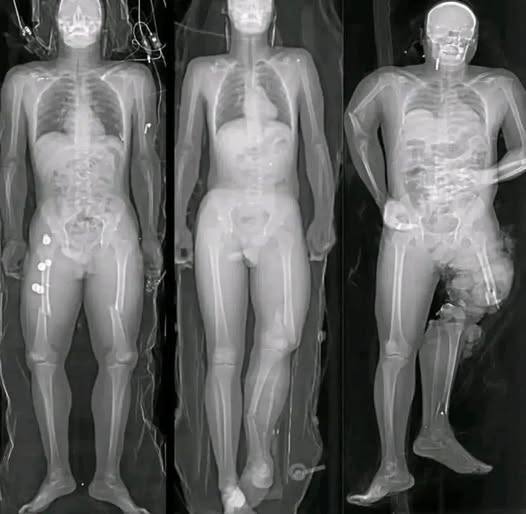

One of the most common claims in viral posts is that COVID vaccines “damage the heart.” This statement oversimplifies and distorts a complex medical issue.

Medical research has identified a small number of myocarditis cases—an inflammation of the heart muscle—following certain mRNA vaccines, particularly among adolescent and young adult males. However, context is critical. These cases are rare, typically mild, and most individuals recover fully with minimal treatment.

Multiple peer-reviewed studies show that the risk of myocarditis from COVID infection itself is significantly higher than the risk associated with vaccination. COVID-19 as a disease has been linked to more severe cardiac complications, including inflammation, blood clots, and long-term heart damage.

In other words, when comparing risks, vaccination reduces overall heart-related danger rather than increasing it.